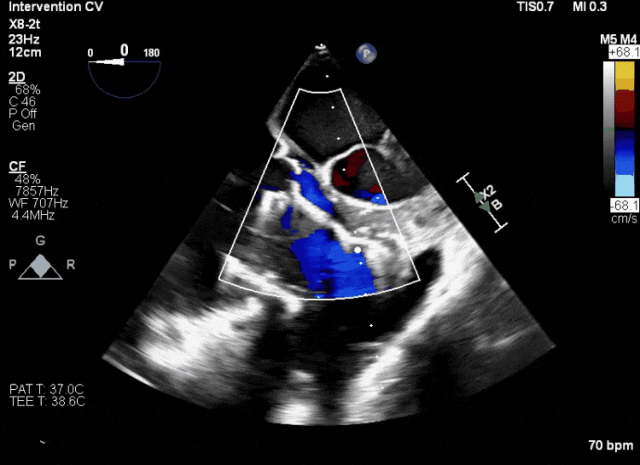

術(shù)后超聲顯示人工瓣膜穩(wěn)定性良好,瓣葉啟閉正常